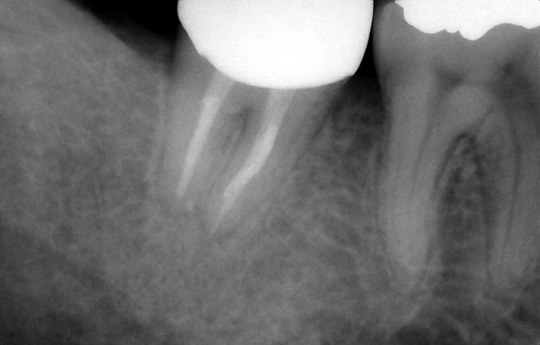

根の先の骨まで感染 骨が溶けている状態

数回の根管治療・根管充填の直後

根管治療終了から3か月 骨が回復傾向

かぶせものをして1年6か月

完全に骨は回復

また、根管(歯根の中にある管)からその周囲の骨に、虫歯由来の細菌が感染すると免疫反応により炎症を起こし骨が溶けます。これを根尖病巣と呼びます。根尖病巣は一種の歯周病であり、痛みが出にくいため放置されることが非常に多いです。そのままにしておくと、根の先の骨が大きく溶けつづけ、抜歯に至ることになります。

それを防ぐためには、感染源である根管の細菌を取り除き感染を止めることで、骨が再生する環境を作ってあげる必要があります。それが根管治療の目的となります。

その環境ができたら速やかに、しっかりと消毒をしたうえで根管を密に充填いたします。最終の土台やかぶせものの隙間から細菌が侵入しても密な根管充填が細菌の再侵入を遅らせてくれます。